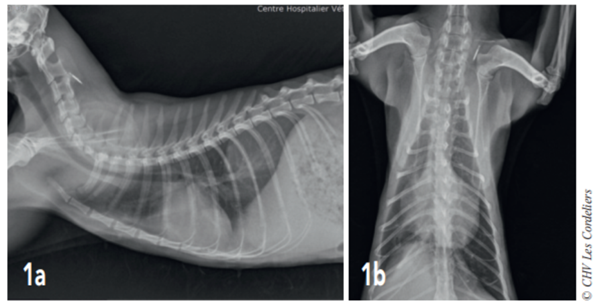

Un examen radiographique thoracique est réalisé (Fig. 1a et 1b) : il montre la présence d’une dilatation modérée des artères pulmonaires plus accentuée dans les lobes crânial droit et caudal gauche ; la silhouette cardiaque est élargie avec un vertebral heart size (VHS) = 9,8 (VU : 7,5 ± 0 3) 2 ; un épanchement pleural modéré associé à un arrondissement des bords pulmonaires responsable d’une opacité interstitielle modérée est mis en évidence. Il est observé une hépatomégalie modérée.

fig 1a et 1b

Fig. 1a – Radiographie thoracique de profil droit du 07/08/2017 : cardiomégalie (VHSM 9,8 ; VU : 7,5 ± 0,3 A.L. Lister), dilatation artérielle pulmonaire modérée, consolidation du lobe pulmonaire moyen droit et épanchement pleural modéré.

Fig. 1b – Radiographie thoracique de face du 07/08/2017 : cardiomégalie (silhouettecardiaque > 2/3 de la largeur thoracique), dilatation artérielle pulmonairemodérée,consolidation du lobe pulmonaire moyen droit et épanchement pleural modéré.